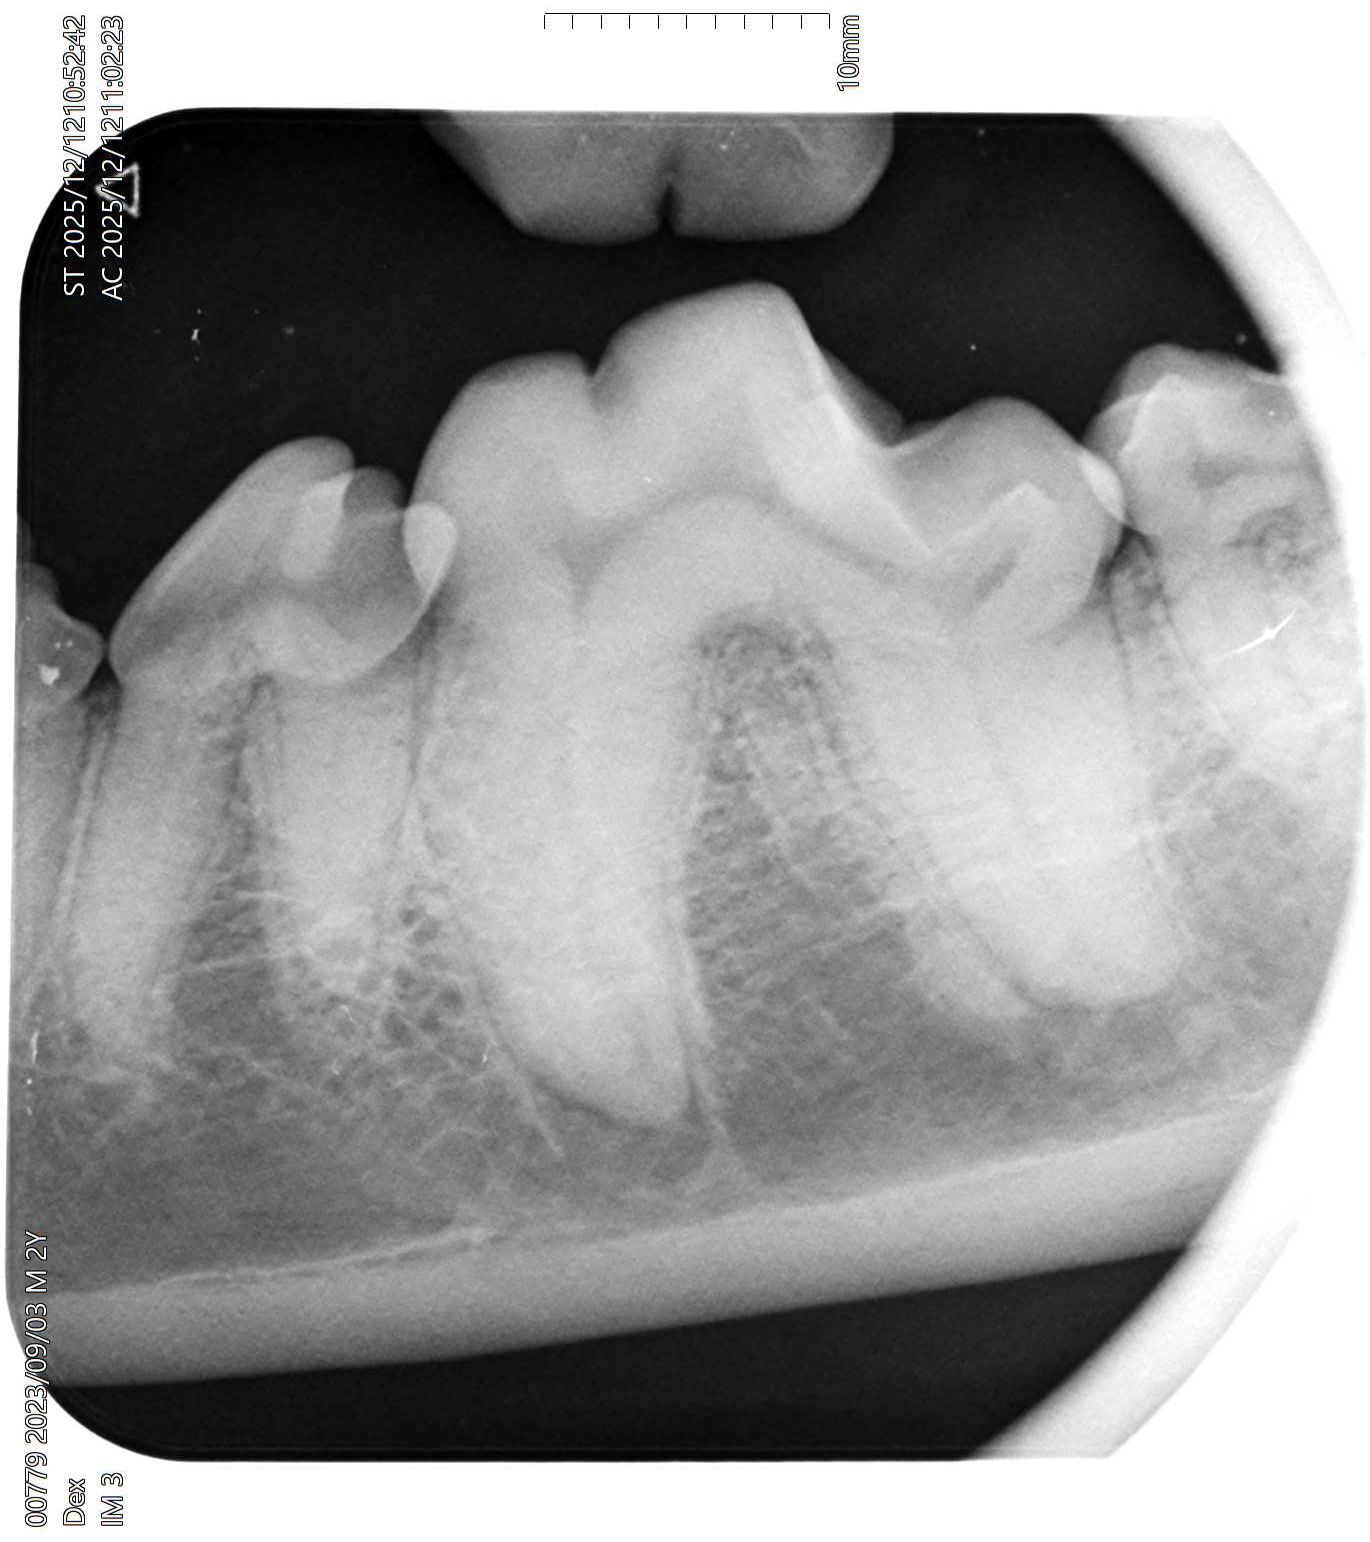

Sinds kort is Dierenkliniek Schinnen in bezit van de modernste tandheelkundige röntgen. Net als bij de tandarts worden plaatjes in de mond gedaan om te kijken of er kiezen of tanden aan het ontsteken zijn.

65 procent van de volwassen honden heeft een of meerdere beginnende of gevorderde ontstekingen van tanden en kiezen. Ze kunnen het alleen niet zeggen. En honden en katten laten het niet snel blijken.

We krijgen goed pas zicht op de staat van het gebit als onder verdoving het tandsteen is verwijderd. Hierna wordt gekeken met een sonde of er te veel ruimte tussen kies en tandkas is. Als dat het geval is dan is zo een wortel verdacht en kunnen we een foto maken om te kijken of we de kies kunnen laten zitten of dat de kies toch getrokken moet worden.